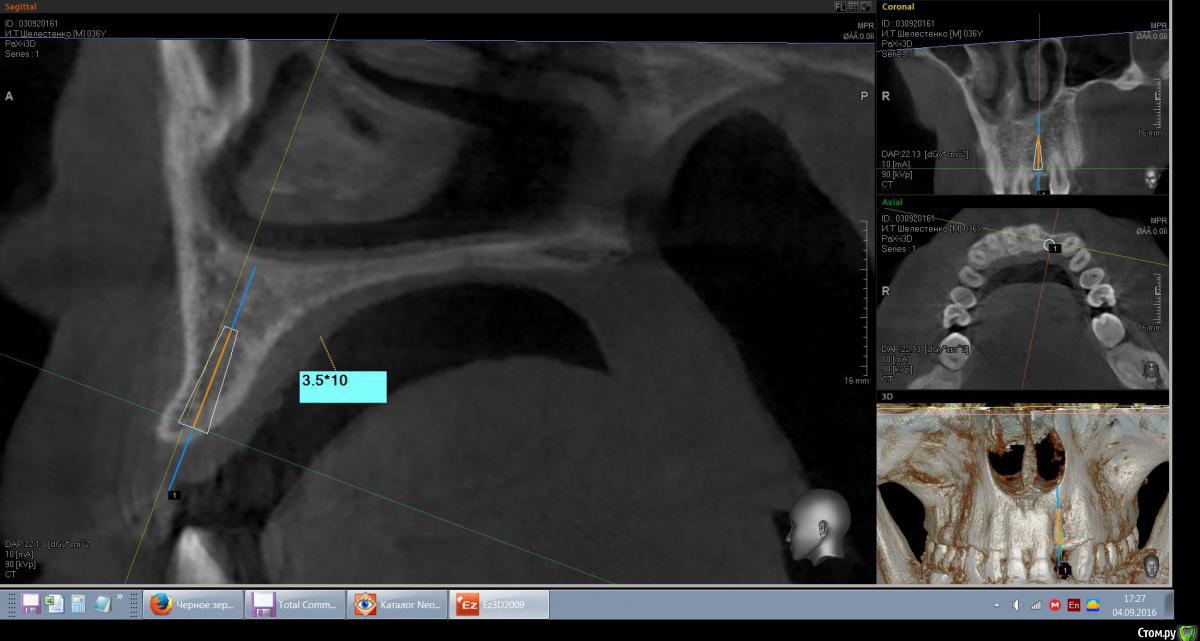

mann Опубликовано 4 сентября, 2016 Автор Поделиться Опубликовано 4 сентября, 2016 Доброе утро!Имеем такую ситуацию. Как лучше и правильно расположить имплант в данной ситуции? Ссылка на комментарий

red_butler Опубликовано 4 сентября, 2016 Поделиться Опубликовано 4 сентября, 2016 вот видите костное предложение на самом деле лучше. Только не нужно так небно ставить. Если сомневаетесь сделайте шаблон или пригласите на операцию ортопеда. И трансп добавьте. Ссылка на комментарий

red_butler Опубликовано 4 сентября, 2016 Поделиться Опубликовано 4 сентября, 2016 а что это? трансплантат.Мне больше нравится позиция на втором снимке, только вестибулярнее и не так глубоко, и я бы ложе готовил эспандерами или чуток расщепился бы Ссылка на комментарий

Эдгар Витальевич Опубликовано 22 октября, 2016 Поделиться Опубликовано 22 октября, 2016 Имплант 3.5мм не узковат будет? Такая же операция предстоит, ширина кости также 4.5 мм. Я планировал 4 мм ставить и костную пластику-титановую мембранку на имплант закрепить под фрмирователь. Ссылка на комментарий